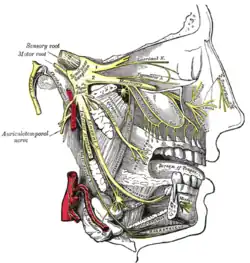

| Trigeminal nerve | |

Nerves

Therapies acting on the vagus nerve (CN X) and the greater occipital nerve have both shown efficacy in managing cluster headache, but the specific roles of these nerves are not well-understood.[6] Two nerves thought to play an important role in CH include the trigeminal nerve and the facial nerve.[30]